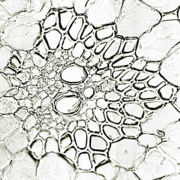

内部形態:鏡検

生姜(ショウキョウ、乾生姜)

JP15:内部形態についての記載はない。

- 生薬の性状

本品は偏圧した不規則な塊状でしばしば分枝する。分枝した各部はやや湾曲した卵形又は長卵形を呈し、長さ2~4cm、径1~2cmである。外面は灰白色~淡灰褐色で、しばしば白粉を付けている。折面はやや繊維性、粉性で、淡黄褐色を呈する。横切面をルーぺ視するとき、皮層と中心柱は明瞭に区別され、その全面に維管束及び分泌物が暗褐色の細点として散在する。 本品は特異なにおいがあり、味は極めて辛い。

- 産地による比較

| 生姜 <中国雲南省> | 生姜 <中国貴州省> | 生姜 <日本> | 生姜 <インド> |

|

|

|

|

| 維管束 | 維管束 | 維管束 | 維管束 |

|

|

|

|